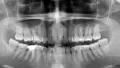

Рекомендовали обратиться к ЛОРу, поскольку стоматолог-хирург никаких проблем со своей стороны не выявил и однозначно подтвердил — все чисто, никаких проблем с его стороны не выявлено. Сделали контрольный снимок, который подтвердил результаты, что это не зубы и не десна.

К сожалению, я не вижу снимок и подтвердить мнение Вашего хирурга не могу. Боль в этой области возможно вызвана растущей восьмёркой, либо проблемой воспалительного характера в области сустава.